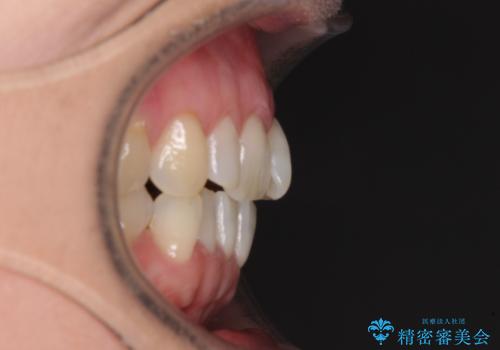

- 前歯の上下スペースによる食べにくさを気にして来院された患者様です。

インビザラインにより上下の前歯の隙間を閉じていくこととしました。

舌の突出癖があると上下前歯にスペースが開くため、矯正治療を機会に舌癖を改善するトレーニングを行ってもらい、矯正治療後の後戻りを防止するように指導しています。